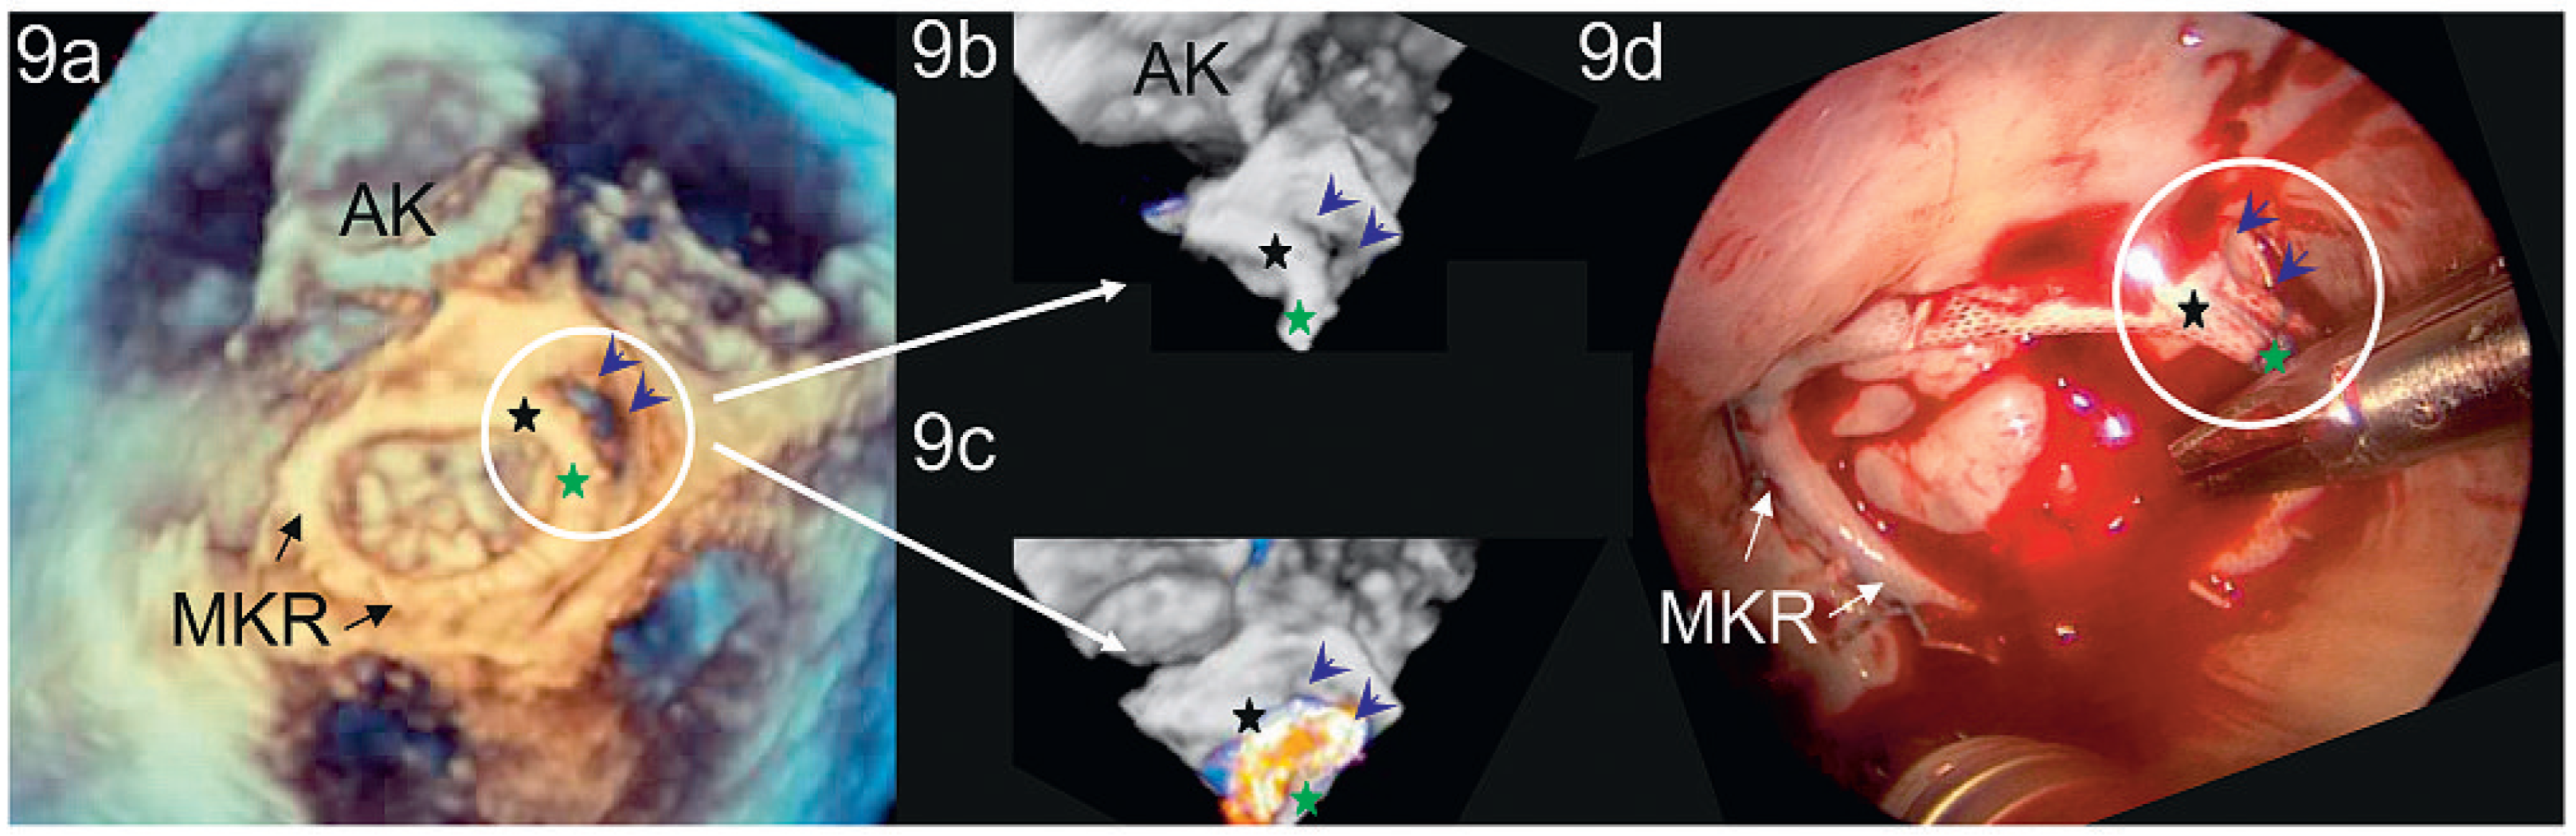

Peri- und postinterventionelle Beurteilung der Mitralklappe